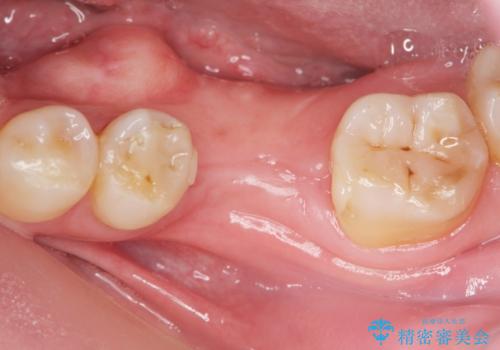

- 歯を破折により失い、インプラント治療を希望され来院されました。

インプラントを埋入し咬合機能を回復するとともに周囲の骨造成も同時に行っていきます。